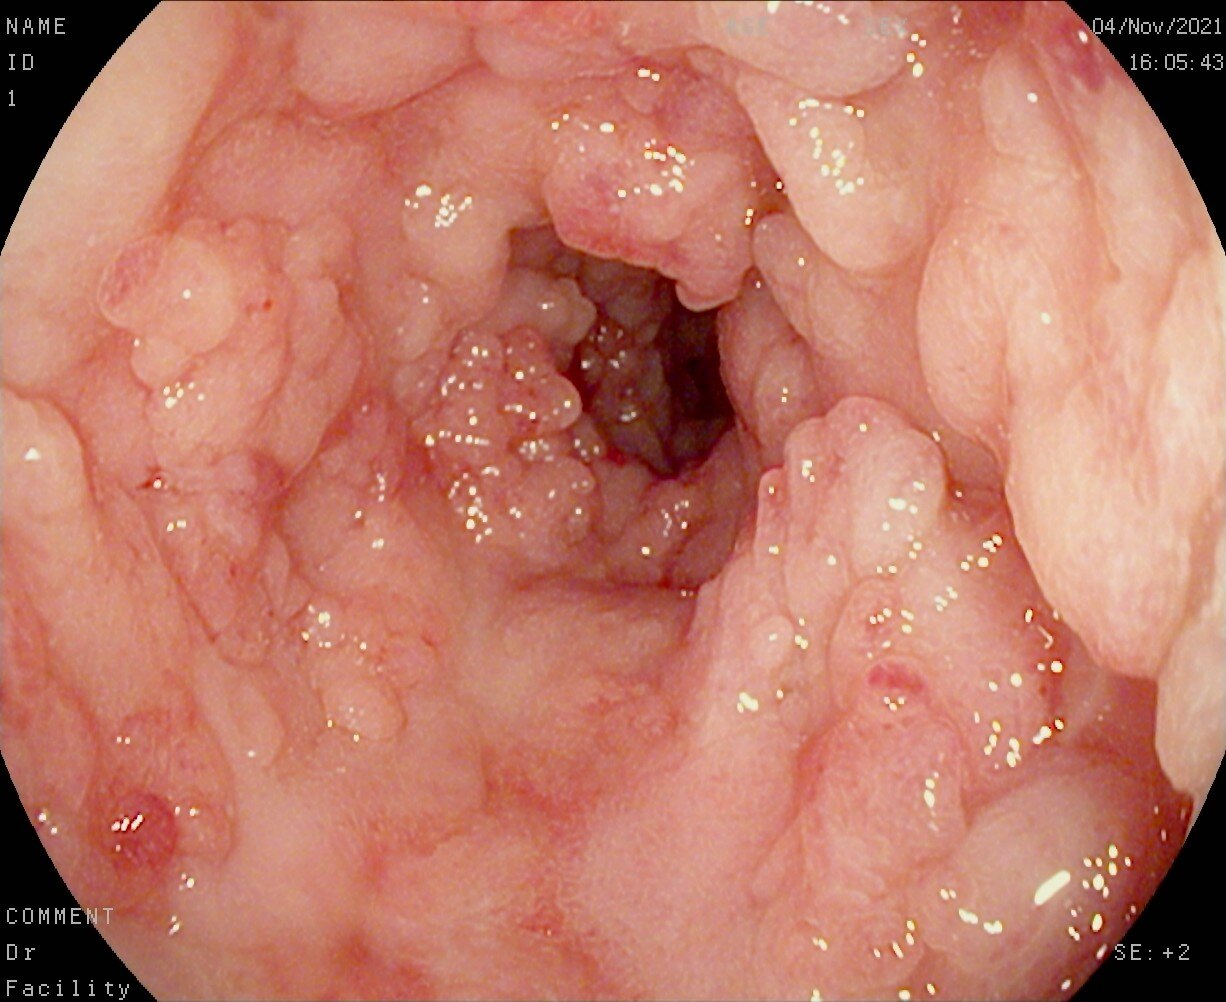

记得第一次听到医生说“克罗恩病”的时候,我的世界仿佛瞬间崩塌。那感觉就像是被命运狠狠地甩了一巴掌。但生活还得继续,药物成了我每天不可或缺的伙伴。一开始,那些药片让我感到恐惧,它们似乎在提醒我,我的身体并不完美。